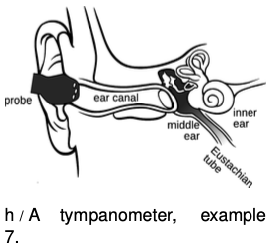

The tympanogram is a medical procedure used to diagnose problems with the middle ear.

The tympanogram is a medical procedure used to diagnose problems with the middle ear.

The middle ear is a chamber, normally filled with air, lying between the eardrum (tympanic membrane) and the inner ear. It contains a tiny set of bones that act as a system of levers to amplify the motion of the eardrum and transmit it to the inner ear. The air pressure in the inner ear is normally equalized via the Eustachian tube, which connects to the throat; when you feel uncomfortable pressure in your ear while flying, it's because the pressure has not yet equalized. Ear infections or allergies can cause the middle ear to become filled with fluid, and the Eustachian tube can also become blocked, so that the pressure in the inner ear cannot become equalized.

The tympanometer has a probe that is inserted into the ear, with several holes. One hole is used to send a 226 Hz sound wave into the ear canal. The ear has evolved so as to transmit a maximum amount of wave motion to the inner ear. Any change in its physical properties will change its behavior from its normal optimum, so that more sound energy than normal is reflected back. A second hole in the probe senses the reflected wave. If the reflection is stronger than normal, there is probably something wrong with the inner ear.

The full physical analysis is fairly complex. The middle ear has some of the characteristics of a mass oscillating on a spring, but it also has some of the characteristics of a medium that carries waves. Crudely, we could imagine that an infected, fluid-filled middle ear would act as a medium that differed greatly from the air in the outer ear, causing a large amount of reflection.

Equally crudely, we could forget about the wave ideas and think of the middle ear purely as a mass on a spring. We expect resonant behavior, and there is in fact such a resonance, which is typically at a frequency of about 600 Hz in adults, so the 226 Hz frequency emitted by the probe is actually quite far from resonance. If the mechanisms of the middle ear are jammed and cannot vibrate, then it is not possible for energy of the incoming sound wave to be turned into energy of vibration in the middle ear, and therefore by conservation of energy we would expect all of the sound to be reflected.

Sometimes the middle ear's mechanisms can get jammed because of abnormally high or low pressure, because the Eustachian tube is blocked and cannot equalize the pressure with the outside environment. Diagnosing such a condition is the purpose of the third hole in the probe, which is used to vary the pressure in the ear canal. The amount of reflection is measured as a function of this pressure. If the reflection is minimized for some value of the pressure that is different than atmospheric pressure, it indicates that that is the value of the pressure in the middle ear; when the pressures are equalized, the forces on the eardrum cancel out, and it can relax to its normal position, unjamming the middle ear's mechanisms.